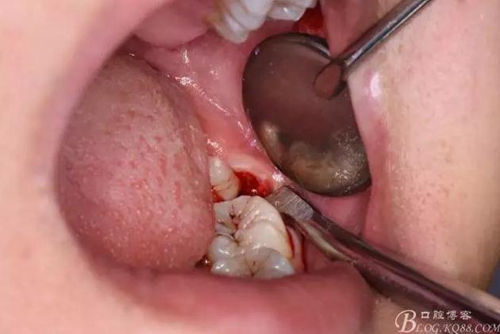

圖8.先從頸部橫斷38

圖9.再把38牙冠近遠(yuǎn)中縱斷